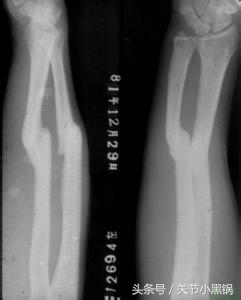

简单理解:石膏固定就是对于一些相对比较小型的骨折或者非负重区域的骨折采用石膏固定或者用于矫形,避免骨折进一步移位的技术或者达到矫形的目的,当然,像上图那样石膏固定了之后也是不能下地行走的!!

石膏固定主要针对的是一些微小的骨折,比如说上肢的骨折等,存在以下缺点:

1、骨折不能绝对固定,可能存在骨折再次移位的可能,甚至因为骨折再次移位损伤周围血管及神经造成严重并发症;

2、石膏固定后,固定的地方会发生肿胀,如果石膏过松可能起不到固定的作用,石膏过紧的话,肢体肿胀明显有可能引起血液循环障碍,小腿及手臂石膏固定引起的最严重的不良反应临床称为骨筋膜室综合征,严重时可能导致截肢;

3、石膏固定过紧或者与皮肤接触部位不平的话可能导致局部压迫缺血,把皮肤压烂造成感染,小孩子或者老年人抵抗力较低的可能感染波及全身,甚至影响生命;

4、石膏固定用于矫形者,比如说小孩子先天性马蹄内翻足的治疗,需要定时更换;

5、石膏固定必须先行手法复位,因为不是直视下复位,因此骨折不能达到解剖复位,有可能存在对线对位的异常,可能存在畸形愈合,影响患者预后;

6、影响生活质量,睡觉的时候也要带着!!!

因此,微小的骨折或者非负重区域的骨折可以考虑石膏固定,但也必须同患者及其家属告知相关替代方案及可能出现的并发症,由患者来选择!